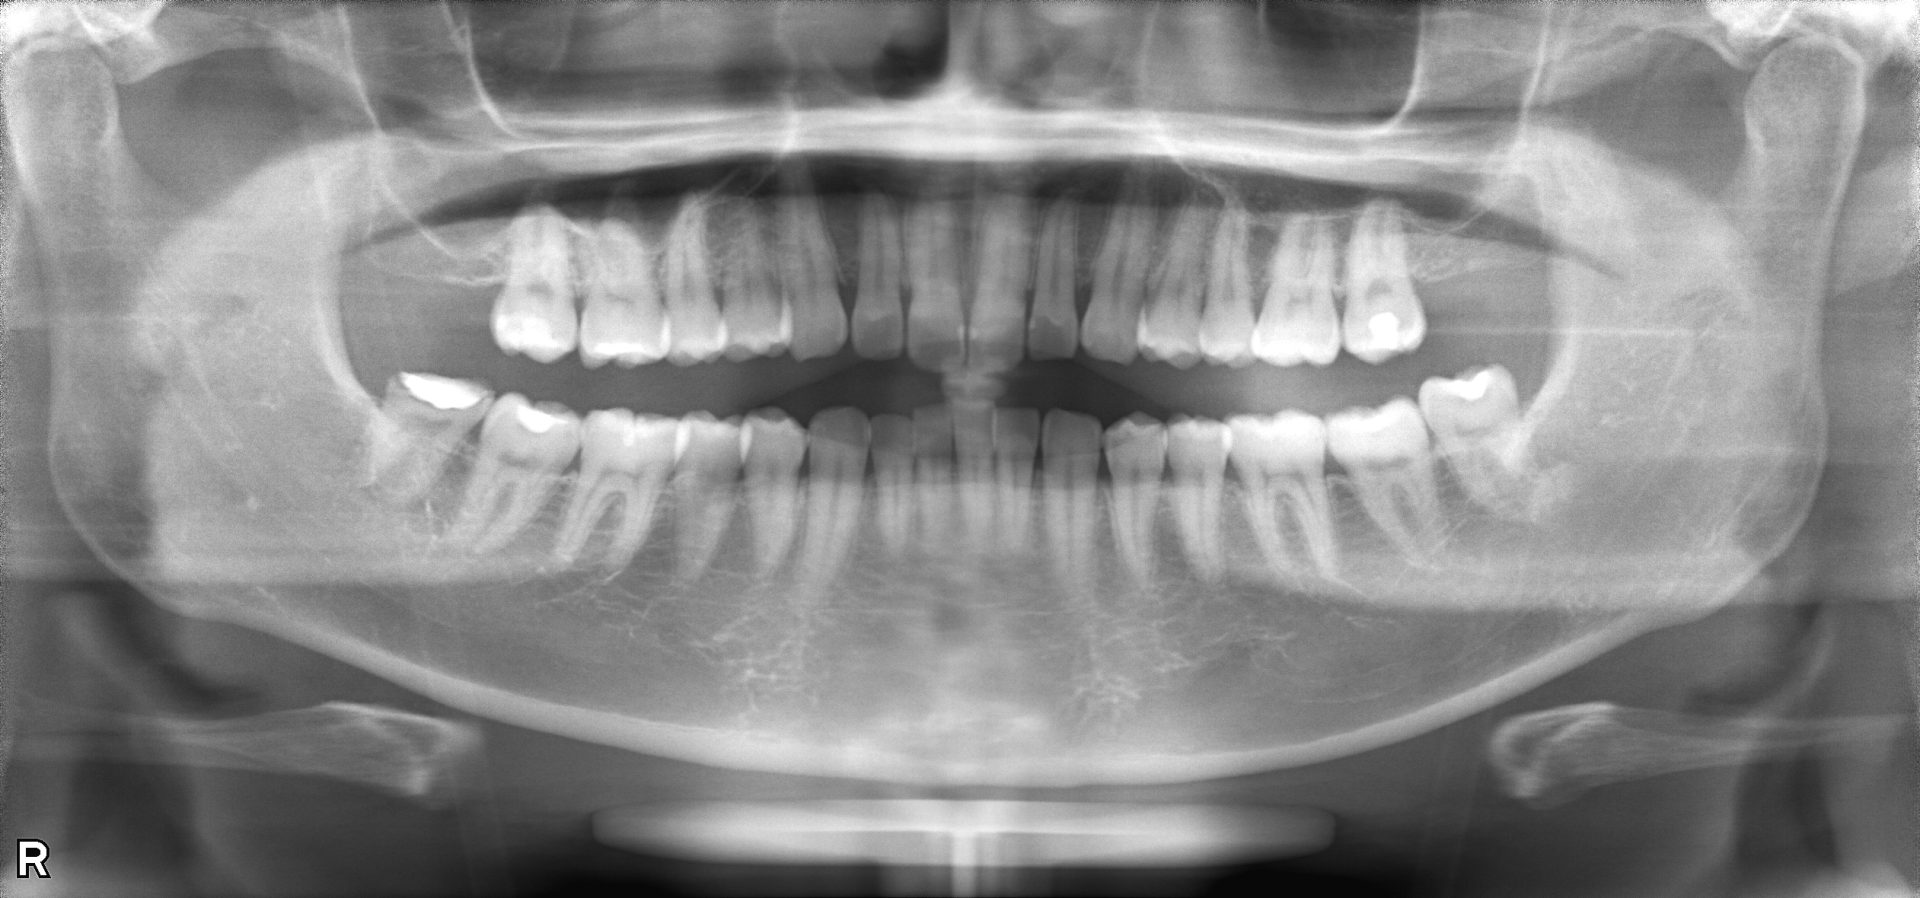

歯科用CT

問題のある部位を立体的な三次元の画像で撮影します。通常のレントゲンでは確認できないような細かな箇所もCTでは確認することができ、正確な診査・診断が可能となります。診断の正確さは治療の成功率に直結します。